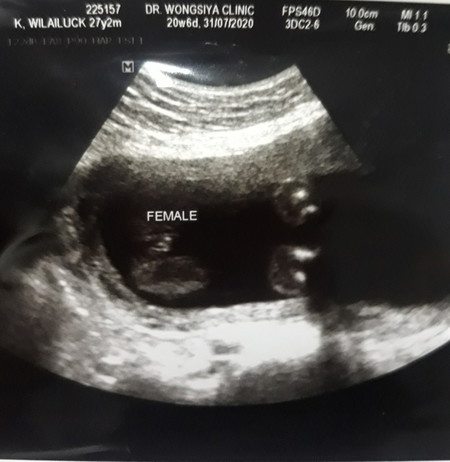

21wแม่ๆว่าแบบนี้ลูกสาวชัวร์ไหมค่ะจะเกิดการซาวผิดพลาดได้ไหมค่ะบ้านนี้อยากได้ลูกสาวมากกลัวผิดหวังค่ะ

Female=คือผู้หญิงค่ะ

สองแคมชัดเจนค่ะ